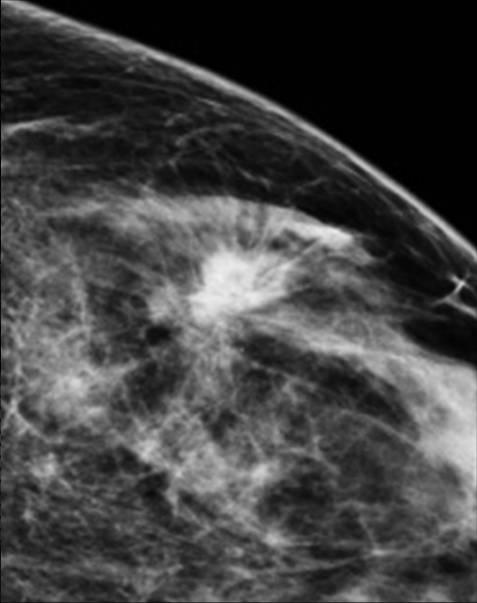

Ung thư vú

Ung thư vú - Ảnh 2

Ung thư vú - Ảnh 3

» Thông tin: Nữ giới – 55 tuổi.

» Lâm sàng: Khối tuyến vú.